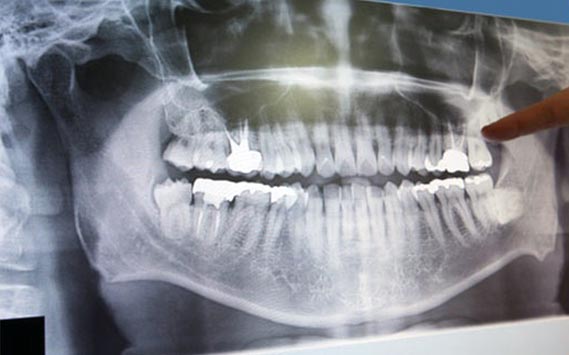

Lo Studio Dentistico Martini è costantemente aggiornato secondo lo stato dell'arte delle più recenti tecnologie in campo medico ed odontoiatrico.